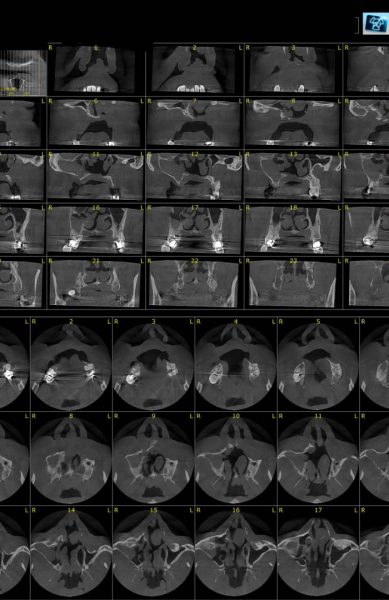

Images of the Radiology

Gallery

The interior pictures of Dr. Yaser Safi Oral and Maxillofacial Radiology Center and sample pictures of the services provided